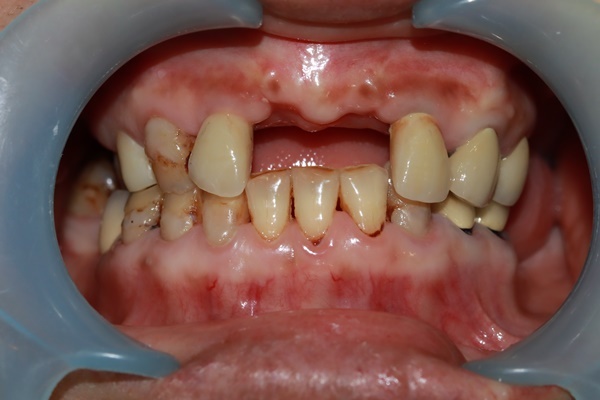

『你這個牙齦退化非常嚴重骨頭流失很多!需要經過翻瓣補骨療程等牙床穩固後才能進行植牙』

其實我已經缺牙好久了,以前雖然有到其他台中牙醫作過治療,但並不是植牙而是在牙齒間搭起牙橋,把兩邊的牙齒磨小,再套上假牙牙套,外觀看起來像有牙齒一樣,但細看其實顏色和正常牙齒有著非常大的落差,除此之外經過歲月多時之後牙齦畏縮磨小牙根也日漸蛀蝕產生口臭!所以我毅然決然找了這間台中牙醫作植牙治療!

只是跟大家分享一下自己在台中植牙心得,也希望各位能好好愛護自己的牙齒~我是因為國小時不懂得刷牙的重要性,上了國中才開始慢慢有刷牙的習慣...不過為時已晚,導致我後來口腔內像經歷過二次世界大戰一樣,滿目瘡痍...